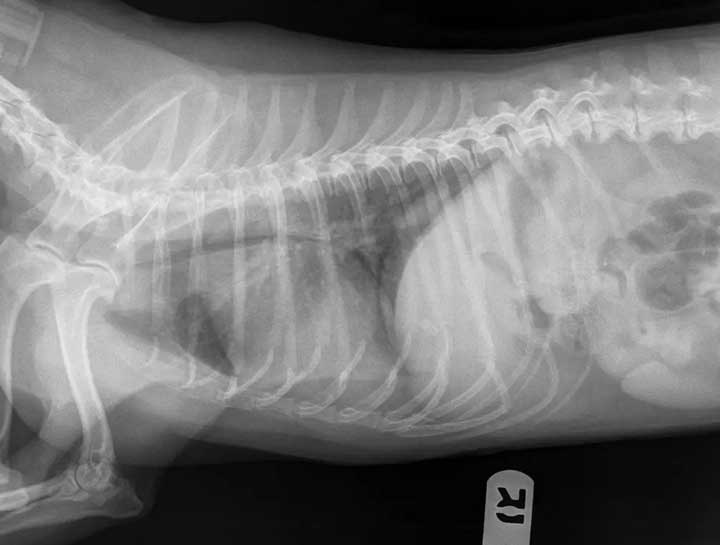

Pet Digital Radiology

Digital x-rays assist in diagnosing illness & injury.